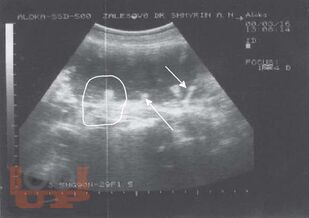

Ультразвуковая диагностика заболеваний толстой кишки

Шмырин А. Н. Ультразвуковая диагностика заболеваний толстой кишки : атлас / А. Н. Шмырин. - М. : Медпрактика-М, 2007. - 48 c. - ISBN 9785988030959. - Текст : электронный // ЭБС "Букап" : [сайт]. - URL : https://www.books-up.ru/ru/book/ultrazvukovaya-diagnostika-zabolevanij-tolstoj-kishki-3675620/ (дата обращения: 22.04.2026). - Режим доступа : по подписке.

Атлас представляет собой учебное пособие для начинающих специалистов и всегда доступный справочник для профессионалов. Форма компоновки материала позволяет быстро получить иллюстрацию патологического процесса и его описание.

Атлас рассчитан на специалистов по ультразвуковой диагностике, проктологов, гастроэнтерологов.